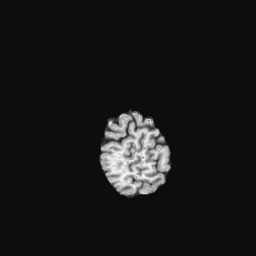

Exp. 1: Segmented adult brain data is used to evaluate our network’s regression performance with known ground truth . 85 brains from the ADNI data set[1] were randomly selected; 70 brains for and 15 brains for . Fig. 2 shows an example slice of the ground truth and the reconstructed .

Reconstructing from initialisation without SVR yields a PSNR of 23.7 1.09; with subsequent SVR the PSNR increases to 29.52.43 when tested on 15 randomly selected test volumes after four iterations of SVR.

Slices, extracted from a correctly registered and reconstructed 3D volume, from the testing data set are presented to the network. The predicted slice is extracted from the same volume, using parameters estimated by SVRNet as shown in Fig. 8 and 9.